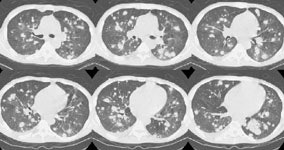

A chest CT also demonstrated the nodules - some of which were distributed along the bronchovascular interstitium, while others were more random. At biopsy, the lesions were found to be recurrent T-cell lymphoma.